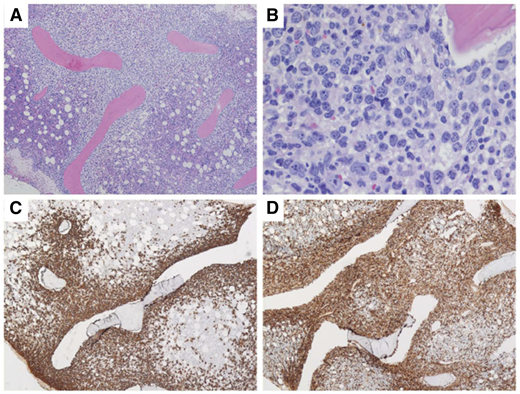

Patient 2 was a 61-year-old man who had presented with a right neck mass 8 years ago. A biopsy showed FL grade 1. He had undergone active observation until several months ago, when he noted right axillary swelling. He was evaluated in the clinic and was found to have an extensive mass in his right axilla and infiltrating the chest wall (Figure 2). A biopsy showed transformation to an aggressive lymphoma with a Ki67 of 95% and sheets of mitotically active intermediate to large cells with a high nucleus/cytoplasm ratio, CD20+CD10+MYC+BCL2+. Subsequent fluorescence in situ hybridization confirmed rearrangements of MYC and BCL2.

Patient with FL transforming to HGBL-DHL/THL, showing massive infiltration of the right chest wall and axillary adenopathy.

Patient with FL transforming to HGBL-DHL/THL, showing massive infiltration of the right chest wall and axillary adenopathy.